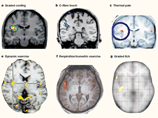

Человек уменьшает ощущение боли, прикасаясь к месту, которое у него болит, установили британские ученые. Они научно подтвердили то, что инстинктивно известно каждому. Об этом сообщает вещательная компания ВВС, ссылаясь на эксперименты, проведенные исследователями из Института когнитивной нейробиологии Университетского колледжа Лондона.

Ученые провели опыт над группой добровольцев, использовав эффект, известный в науке как "термическая иллюзия ожога". Чтобы достичь его, человек должен опустить указательный и безымянный пальцы руки в теплую воду, а указательный палец той же руки - в холодную воду.

При этом средний палец начинает испытывать ощущение сильного жжения, которое на самом деле представляет собой иллюзию, вызванную реакцией нервной системы на раздражитель.

Сразу после этого участников эксперимента просили прикоснуться безымянным, указательным и средним пальцем одной руки к тем же пальцам другой. После этого все участники эксперимента сказали, что ощущение жжения в среднем пальце уменьшилось.

При помощи научных методов удалось установить, что интенсивность болевых ощущений уменьшалась в среднем на 64 процента. Также выяснилось, что если к "больному" месту прикасался другой человек, облегчения не наступало.

Ученые объясняют этот феномен тем, что интенсивность боли зависит не только от силы ее источника, но и от того, как она воспринимается мозгом, сообщает ИТАР-ТАСС.

"Боль это не просто сигнал, который идет от тела к мозгу, - поясняет один из авторов работы, исследовательница из Университетского колледжа Марджолейн Каммерс. - Боль преобразовывается в мозгу, в зависимости от того, как наш мозг представляет себе нынешнее состояние нашего тела".